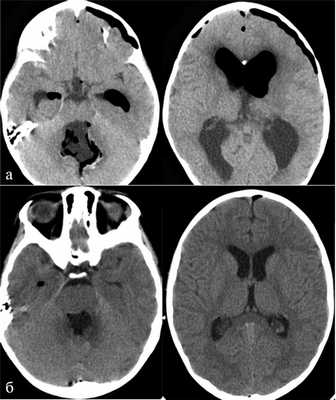

Наш опыт показывает, что при удовлетворительном предоперационном состоянии пациента, отсутствии данных за инфильтрацию ствола во время операции и значимых отклонений в течении анестезии, пациенты, оперированные в положении «лежа», могут после пробуждения быть переведены в общее отделение. Уровень их активности и бодрствования в первые несколько суток, по нашим субъективным оценкам, выше, чем у аналогичных пациентов, оперированных в положении «сидя». Основным объяснением этого феномена мы видим меньшую степень пневмоцефалии и особенно меньшее количество воздуха в желудочковой системе (рис. 7). Рис. 7. Количество интракраниального воздуха в 1-е сутки после операции в зависимости от положения пациента на операционном столе. а — КТ пациента после удаления медуллобластомы червя мозжечка и IV желудочка в положении «сидя». Обращает на себя внимание выраженная пневмоцефалия, сглаженность и сдавленность субарахноидальных пространств, несмотря на наличие у пациента функционирующего НВД, установленного в начале операции; б — КТ пациента после удаления медуллобластомы червя мозжечка и IV желудочка в положении «лежа». Отмечается минимальное количество интракраниального воздуха, хорошая релаксация желудочковой системы, широкие субарахноидальные пространства. Следует отметить, что в положении лежа мы не используем периоперационный НВД вне зависимости от степени выраженности гидроцефалии. Возможно, некоторый вклад в раннюю активизацию вносят и отсутствие НВД, и меньший объем диссекции мягких тканей (менее выраженный болевой синдром). Некоторые пациенты могли быть выписаны на 2—3-и сутки после операции в хорошем состоянии. Такой ранней выписки мы не наблюдали ни у одного пациента, оперированного в положении «сидя».